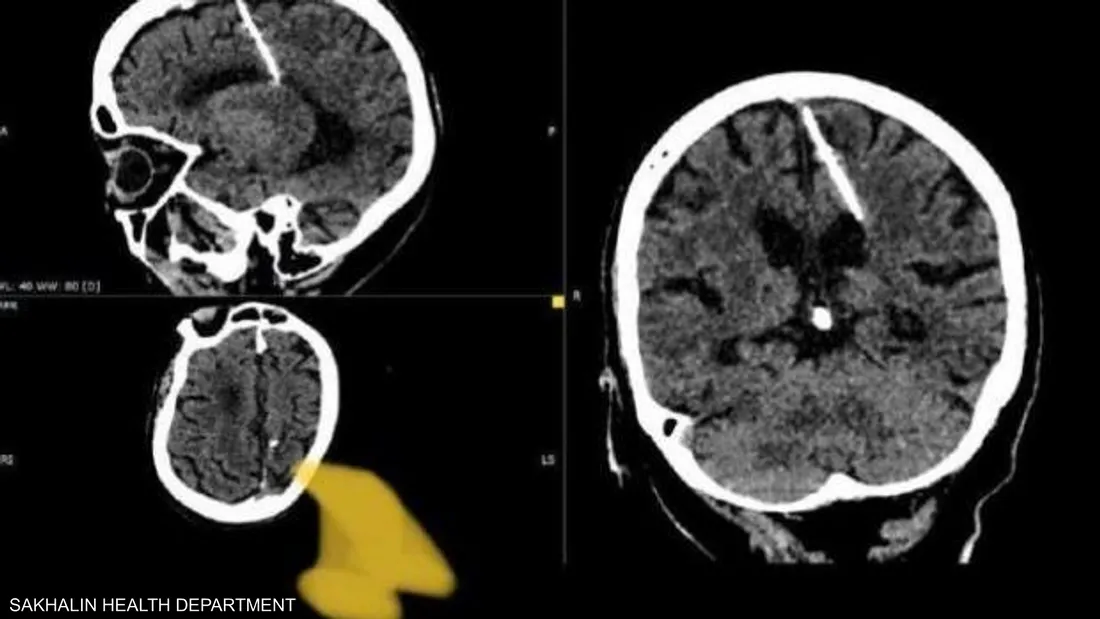

عثر أطباء خلال فحص بالتصوير المقطعي على إبرة بطول ثلاثة سنتيمترات موجودة منذ ثمانين عاماً داخل دماغ امرأة مسنّة في أقصى الشرق الروسي.

ويعتقد الأطباء أن المرأة تعرضت لمحاولة قتل فاشلة نفذها والداها خلال طفولتها، وقالوا إنهم لن يحاولوا إزالة الإبرة خشية أن يفاقم ذلك حالتها.

وأضافت أن والديها قررا على الأرجح التخلص من طفلتهما خلال الحرب العالمية الثانية، لأنها كانت تعيش مع إبرة يبلغ طولها ثلاثة سنتيمترات “منذ ولادتها”.